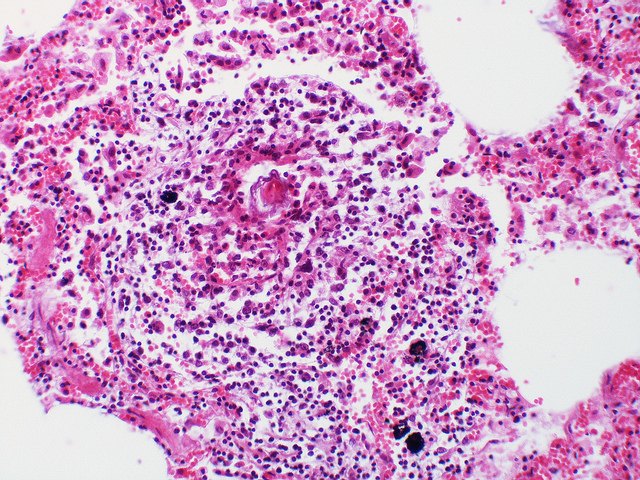

Inflammation, parasites, and cancer have long been interconnected. We have included some images of interest showing some of the known human blood-dwelling parasites, Schistosoma induced cancer, and prostate cancer pathology. For more research supporting links between cancer and infections we suggest these publications:Chronic Bacterial Infections and Cancer Risk Colorectal Cancer and Schistosoma Schistosoma Prostate Case Report #1 Schistosoma Prostate Case Report #2 Parasitic Infection and Cancer

Granuloma surrounding a Schistosoma egg (Flickr user Yale Rosen)